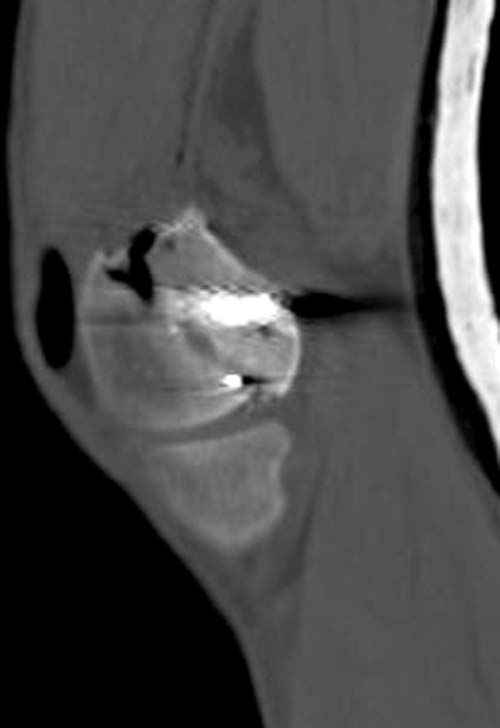

По Густило и Андерсену все high-energy переломы являются III не зависимо от степени повреждения мягких тканей. Plating такого перелома на второй день кажется немного рискованным хотя "победителей не судят". Судя по КТ, медиальный мыщелок стабильный, насколько необходимо было его фиксировать?

Идеальная репозиция?! -На снимочке A-P проeкции видна "зазубрина" по суставной поверхности, латеральный снимок - тоже не идеально.